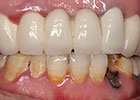

為美做烤瓷牙導致牙根發炎、腐爛,來深圳種牙信賴麥芽口腔,讓我缺牙重生。